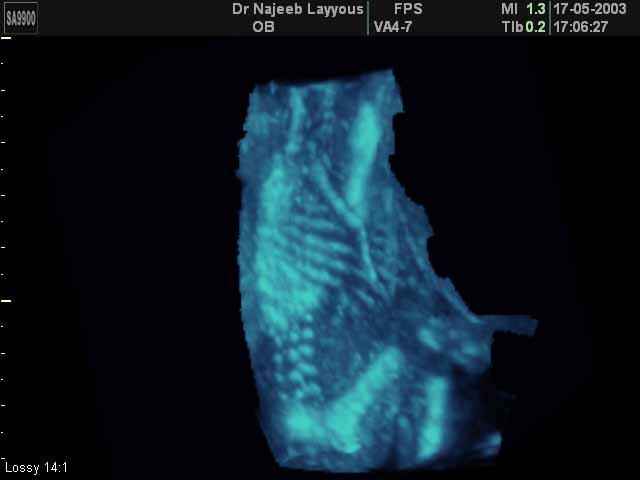

- صور للهيكل العظمي للجنين

صور للهيكل العظمي للجنين بجهاز الالتراساوند ثلاثي الأبعاد | الدكتور نجيب ليوس